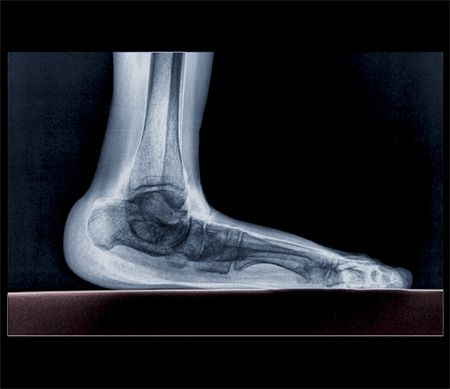

提及身体健康,默默无闻的双脚,大概是最容易被忽视的部位之一,事实上双脚不仅是“第二心脏”,还是全身健康的“放大镜”。双脚出现哪些变化,可能是身体敲响的警钟呢?这就带你去了解一下!脚部皮肤干燥的罪魁祸首不仅仅是脚癣或过敏,很可能是血液循环不畅所致,使脚部无法接收足够的供血。甲状腺素是调节新陈代谢的“主力干将”,其分泌不足会导致新陈代谢和体温调节出现异常,身体产生热量的能力大受影响,致使手脚冰凉。还有可能是血液循环不好,动脉闭塞、糖尿病都可能引起脚部冰凉。麻木多与神经病变有关,如果你的脚时常出现麻木感,这可能是由于足部、脚踝或腰椎的神经受压或神经炎所引起的。需要注意的是,短暂发麻可能是鞋子太紧造成的,不必担心。起床或从椅子上站起来时,脚后跟的底部出现剧烈疼痛。行走数步稍缓解,随后疼痛又加重。运动增加、穿太紧或太旧的鞋、穿人字拖等都会加重症状。关节上突然发作的红肿热痛需及时就医,这可能是痛风、关节炎、感染和外伤所致。此外,患有呼吸道疾病、淋巴水肿和类风湿性关节炎也会导致脚指甲发黄。肾脏有筛选营养素的作用,一旦工作失常,体液就难以及时排出体外,导致浮肿,脚部肿胀最为明显。还有可能是踝关节炎,曾经崴脚留下的后遗症,引起滑膜炎、软骨损伤和韧带损伤所致。黑色素瘤可能出现在身体任何部位,包括脚趾,所以检查皮肤时不要漏过双脚,一旦有不明原因的黑痣出现,可能是皮肤癌的征兆。肺纤维化和肺癌等肺病会导致血液流向脚指甲小血管,引起组织膨胀,从而导致脚趾更圆更扁(临床上叫杵状趾)。心脏病、肝病和消化系统疾病,以及某些感染,也会导致脚趾变形。俗话说:“天天泡脚,胜吃补药。”热水泡脚可加快血液循环,有利于消除腿脚酸麻、胀痛不适等疲劳症状。建议养成每晚睡前热水泡脚的好习惯,但注意水温和时间,防止烫伤足部。运动能够锻炼脚部肌肉,是保护双脚的好办法。建议每天坚持小腿和足部运动30~60分钟,提脚跟、伸膝勾脚等都可以。